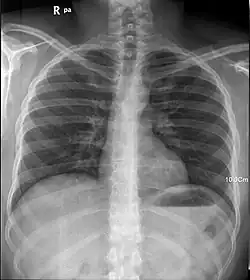

Desde que Röntgen descubrió que los rayos X permiten captar estructuras óseas, se ha desarrollado la tecnología necesaria para su uso en medicina. La radiología es la especialidad médica que emplea la radiografía como ayuda en el diagnóstico médico, en la práctica, el uso más extendido de los rayos X.

Los rayos X son especialmente útiles en la detección de enfermedades del esqueleto, aunque también se utilizan para diagnosticar enfermedades de los tejidos blandos, como la neumonía, cáncer de pulmón, edema pulmonar, abscesos.

En otros casos, el uso de rayos X tiene más limitaciones, como por ejemplo en la observación del cerebro o los músculos. Las alternativas en estos casos incluyen la tomografía axial computarizada, la resonancia magnética nuclear o los ultrasonidos.

Los rayos X también se usan en procedimientos en tiempo real, tales como la angiografía, o en estudios de contraste.